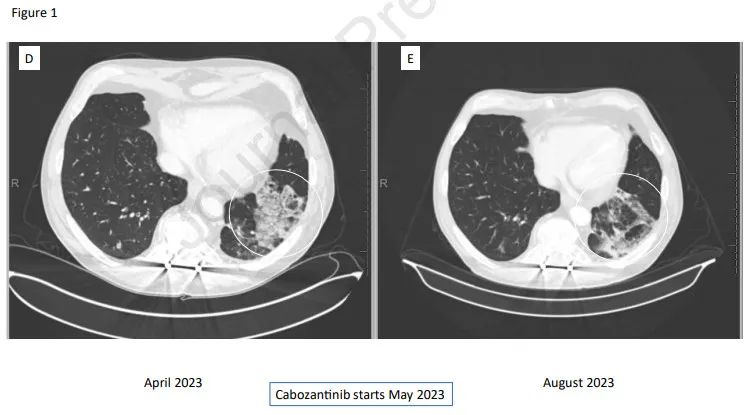

停用瑞普替尼,开始使用每天40mg卡博替尼。患者最初难以耐受这种治疗,需要短暂的治疗暂停和减量,但一个月后剂量重新增加到每日40mg。卡博替尼治疗开始后3个月进行的第一次CT扫描显示,患者获得部分缓解(PR)(图1D和图E)。到目前为止,治疗缓解已维持了7个月。

图1D和图E:CT扫描显示卡博替尼治疗达到部分缓解